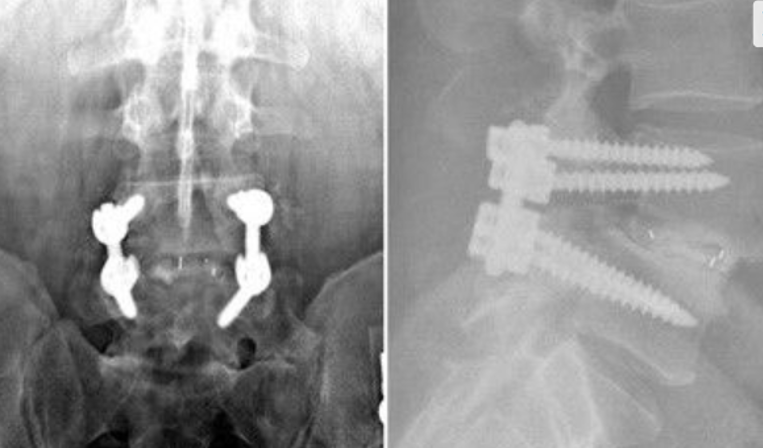

After Surgery Results

Transforaminal Lumbar Interbody Fusion – performed from the back through a small opening, allowing access to the disc space with minimal disruption to spinal structures.

Oblique Lumbar Interbody Fusion – performed from the side, avoiding major back muscles and reducing tissue damage while providing excellent disc space access.

Anterior Lumbar Interbody Fusion – performed through the abdomen, placing implants in front of the spine for optimal disc space restoration.